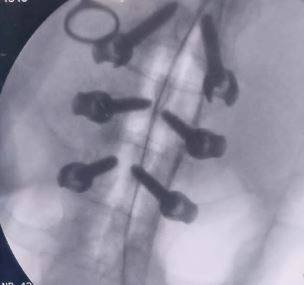

فى اليوم التالي تم عمل لسته عمليات جراحيه ما بين الجراحات المتقدمة لتثبيت الفقرات القطنية و بعدها تم عمل مناظر مخي استكشافي لبطينات طفله بالغه من العمر ١٤ يوم تعانى من استسقاء مستعصي ببطينات المخ وتم لها كى لضفيره الشعيرات الدموية المخية وفك التصاقات بطينات المخ.

اليوم التالي تم اجراء جراحه دقيقه لمريض يعانى من خذل نصفى بالطرفين السفلين ناتج عن اشتباه ورم ثانوي بالفقرات الصدرية ضاغط على الحبل الشوكي وتم اجراء جراحه دقيقه لتوسيع القناه العصبية الصدرية و اخذ عينه من الورم للتحليل؛ على الفور بعد الاجراء تحسن الخذل الموجود لدى المريض والنتيجة كانت مرضيه تماما للمريض.